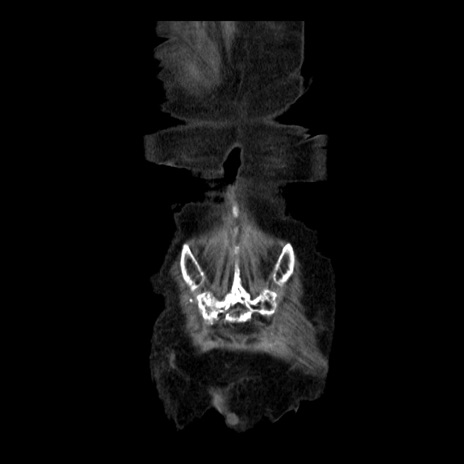

症例14(冠状断像)

【症例】 90歳代女性

【主訴】 腹痛・嘔吐

【現病歴】今朝から左側腹部痛を認めた。 経過観察していたが、嘔吐を認めたため来院。

【既往歴】 子宮癌術後

【身体所見】 意識清明、BP 127/54mmHg、P 98bpm Sp02 95%(RA)、BT 35.8°C、腹部平坦・軟腸ぜん動音聴取良好、右下腹部圧痛(+) 反跳痛なし

【データ】WBC 9800、CRP 0.46